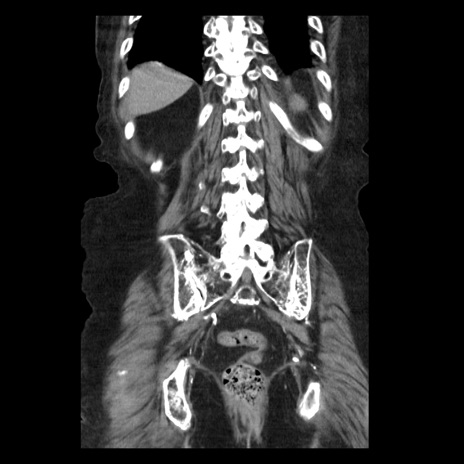

症例14(冠状断像)

【症例】 90歳代女性

【主訴】 腹痛・嘔吐

【現病歴】今朝から左側腹部痛を認めた。 経過観察していたが、嘔吐を認めたため来院。

【既往歴】 子宮癌術後

【身体所見】 意識清明、BP 127/54mmHg、P 98bpm Sp02 95%(RA)、BT 35.8°C、腹部平坦・軟腸ぜん動音聴取良好、右下腹部圧痛(+) 反跳痛なし

【データ】WBC 9800、CRP 0.46